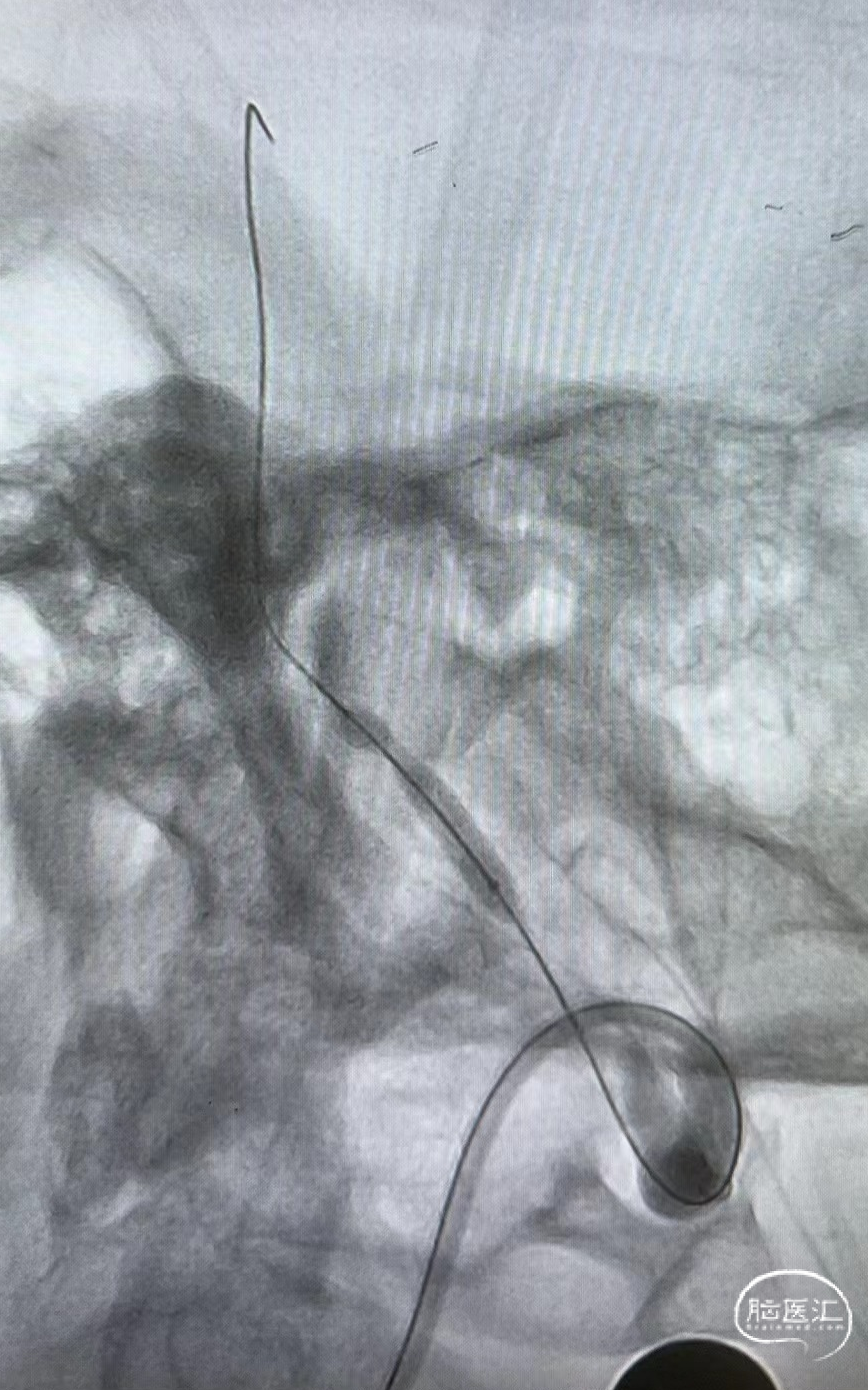

远端通路导管到位。

微导丝通过病变。